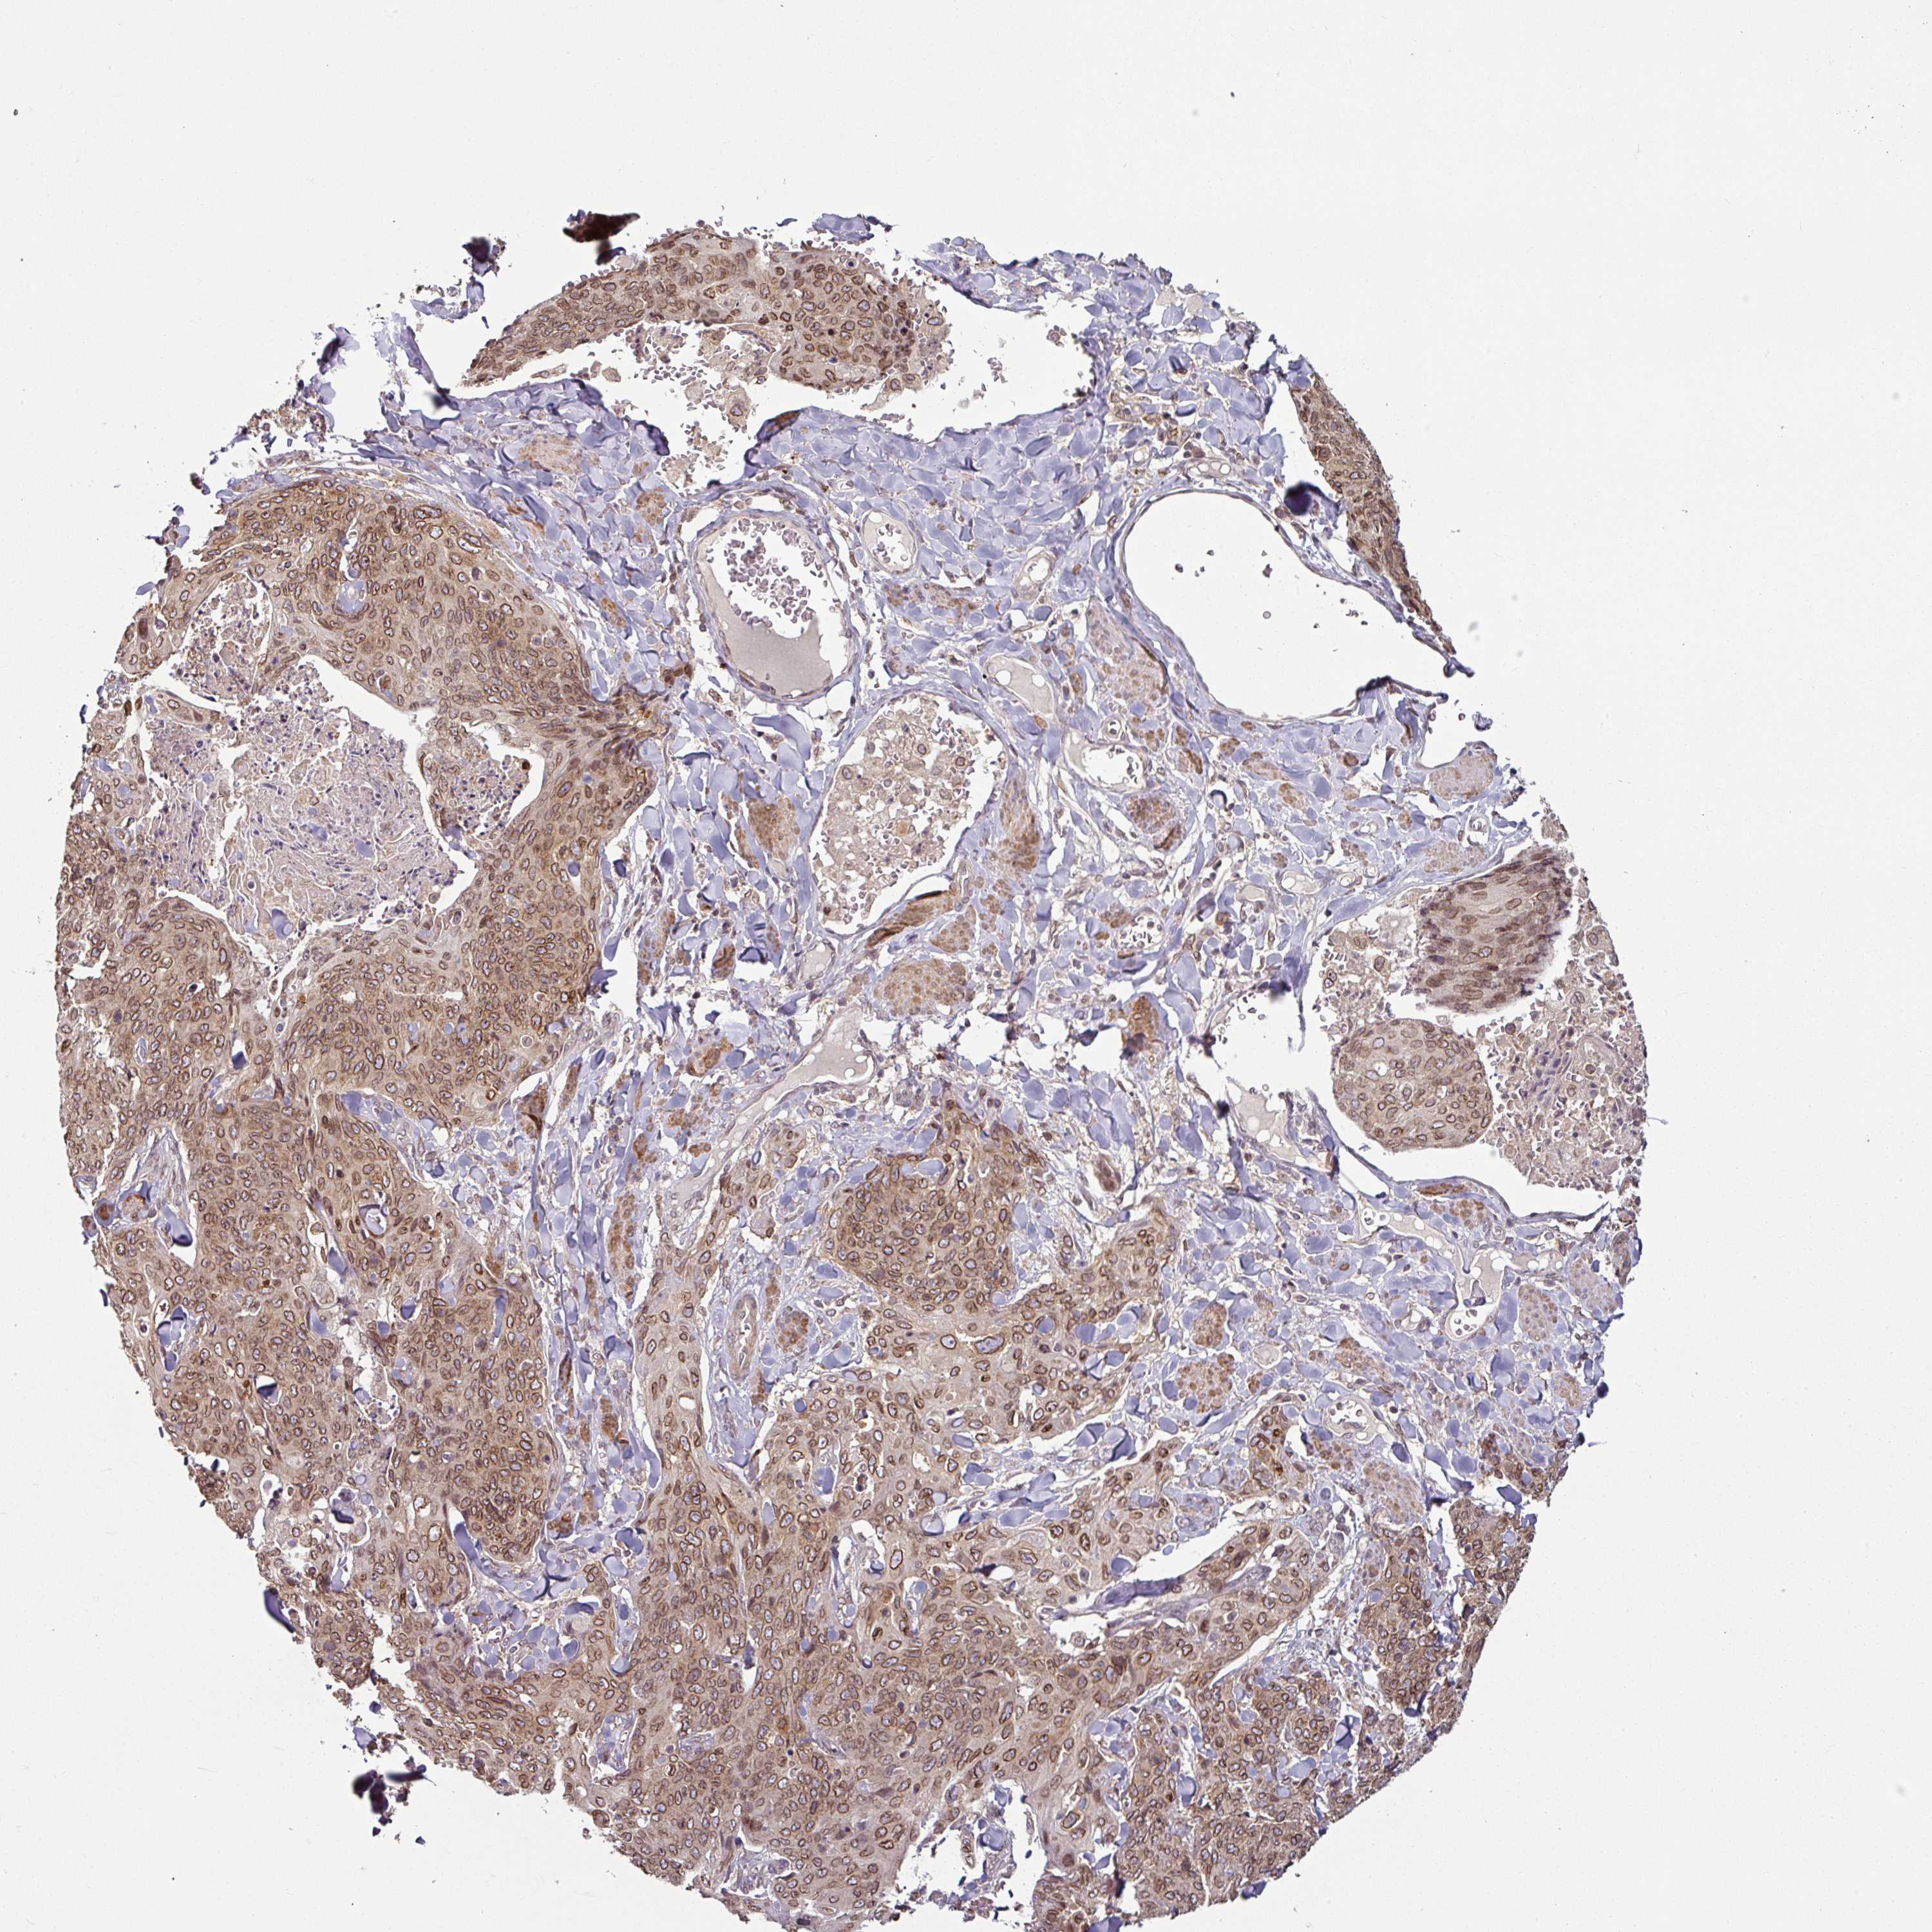

Basal cell and squamous cell cancer

SKIN CANCER - Protein expressioni

A mouse-over function shows sample information and annotation data. Click on an image to view it in a full screen mode. Samples can be filtered based on level of antibody staining by selecting one or several of the following categories: high, medium, low and not detected. The assay and annotation is described here.

Antibody stainingi

Antibody staining in the annotated cell types in the current human tissue is reported as not detected, low, medium, or high, based on conventional immunohistochemistry profiling in selected tissues. This score is based on the combination of the staining intensity and fraction of stained cells.

Each image is clickable and will lead to virtual microscopy that enables deeper exploration of all samples and also displays staining intensity scores, fraction scores and subcellular localization as well as patient and tissue information for each sample.

Antibody HPA050110

Antibody CAB004293

Squamous cell carcinoma, NOS